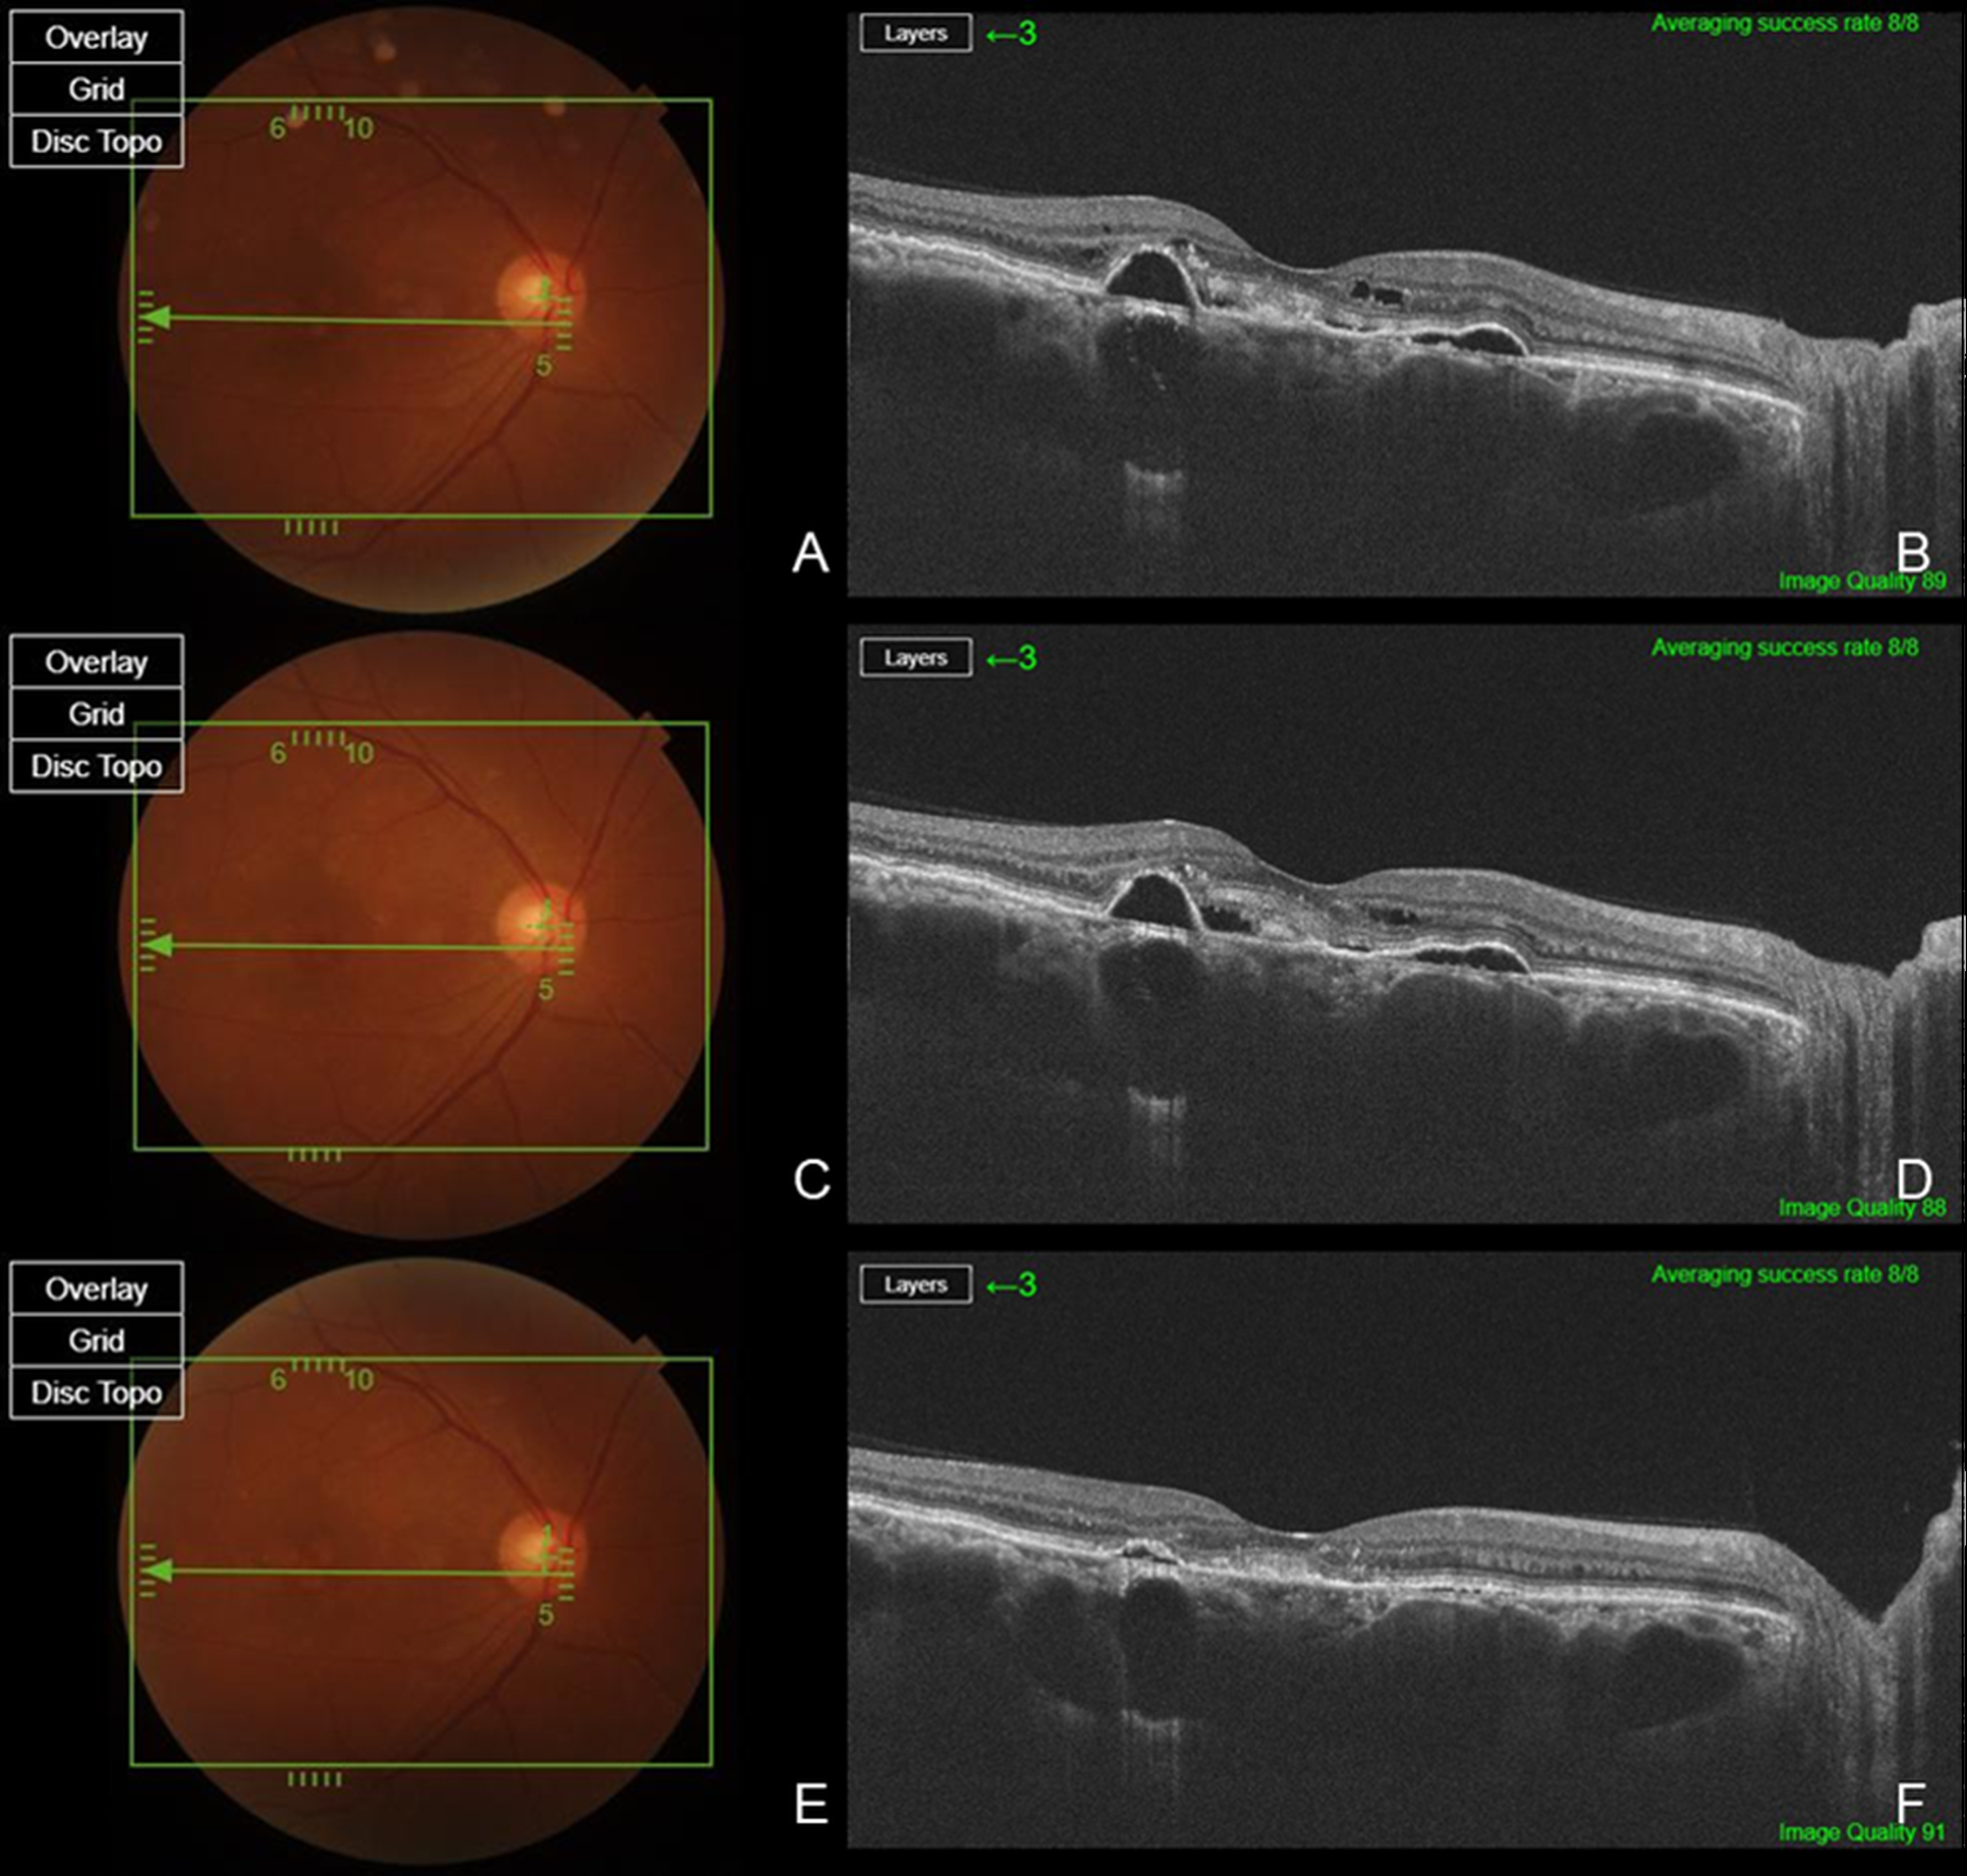

Figure 1. Multimodal retinal imaging in a treatment-naïve patient with chronic central serous chorioretinopathy (cCSC). Baseline fundus photography (A) and swept source (SS)-optical coherence tomography (OCT) (B) show mild pigment epithelial detachment (PED) and subretinal fluid (SRF) at the macula. At one month after intravitreal injection of brolucizumab, fundus photography (C) and SS-OCT (D) demonstrate complete resolution of SRF and significant reduction in PED height. Fluorescein angiography (E) reveals minimal leakage without evidence of pachychoroid neovasculopathy (PNV) or polypoidal lesions, supporting the diagnosis of uncomplicated cCSC. Subfoveal choroidal thickness (SCT) decreased from 401 μm at baseline (B) to 208 μm (D) after injection.

Figure 2. Therapeutic response after switching to brolucizumab in a previously treated patient with bevacizumab. Baseline fundus photography (A) and SS-OCT (B) demonstrate persistent SRF and PED, despite six prior intravitreal bevacizumab injections. One month after the last bevacizumab injection, SRF and PED remain unchanged, as shown by fundus photography (C) and SS-OCT (D). Following a switch to intravitreal bolucizumab, fundus photography (E) and SS-OCT (F) at one month post-injection reveal complete resolution of SRF and significant reduction in PED height, indicating superior anatomical efficacy of brolucizumab in this refractory case. While the SCT value remained nearly unchanged from a baseline of 705 μm (B) to 701 μm (D) after bevacizumab injection, it decreased to 643 μm (F) one month after brolucizumab administration.